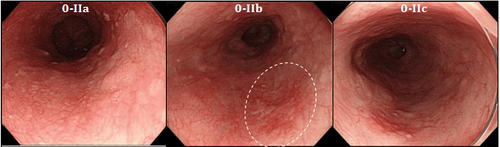

Ung thư thực quản giai đoạn sớm được nhìn thấy qua nội soi

Việc chẩn đoán ung thư thực quản và các tổn thương tiền ác tính của nó hiện chỉ giới hạn trong nội soi và phân tích sinh thiết sau đó. Nội soi là một thủ thuật chẩn đoán xâm lấn cao và tốn kém và là kỹ thuật chẩn đoán tiêu chuẩn vàng hiện nay đối với ung thư thực quản và các tổn thương tiền ung thư của nó. Nội soi ánh sáng trắng tiêu chuẩn bị giới hạn trong phạm vi của nó, chỉ giới hạn trong việc xác định các bất thường vĩ mô có thể chỉ ra ung thư, chẳng hạn như nốt và vết loét, do đó không xác định được các tổn thương sớm có vẻ bình thường về mặt đại thể. Trong khi thực quản Barrett có thể nhìn thấy qua nội soi, thì việc loạn sản trong đoạn Barrett khó xác định hơn vì các tổn thương thường phẳng và khó phân biệt với biểu mô trụ không loạn sản xung quanh .